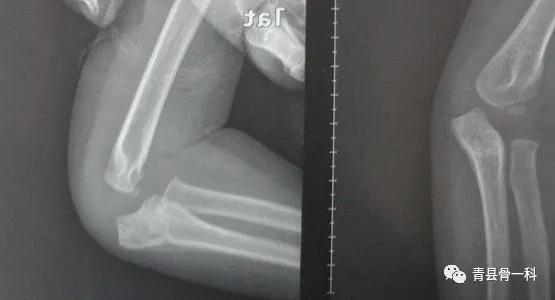

儿童骨折的特点:1、儿童骨血液较丰富,矿物质、纤维组织量多,多出现青枝骨折、皱褶骨折和弯曲骨折;2、儿童的骨膜较厚,矿物质较多,少有粉碎性骨折,若移位明显,张力侧骨膜断裂,另一侧也相对完整,这有利于复位后的稳定及愈合,儿童骨骺损伤则相对严重;3、儿童软骨在X光片不显影,故损伤后要查CT或MRI。

如何简单的判断儿童骨折,首先要向患儿或其家长询问受伤史及肿处局部的情况,比如肿胀、疼痛、压痛、瘀斑,以及是否有明显的有畸形、骨擦音。以上能一目了然可以判断,当然,要借助X光片,必要时还要增加CT或MRI。

儿童骨折常规的处理方法,有手法复位、小夹板固定、石膏固定,皮肤牵引、骨牵引、闭合复位,克氏针固定、弹性钉固定或者外固定架固定,必要的时候切开复位内固定。